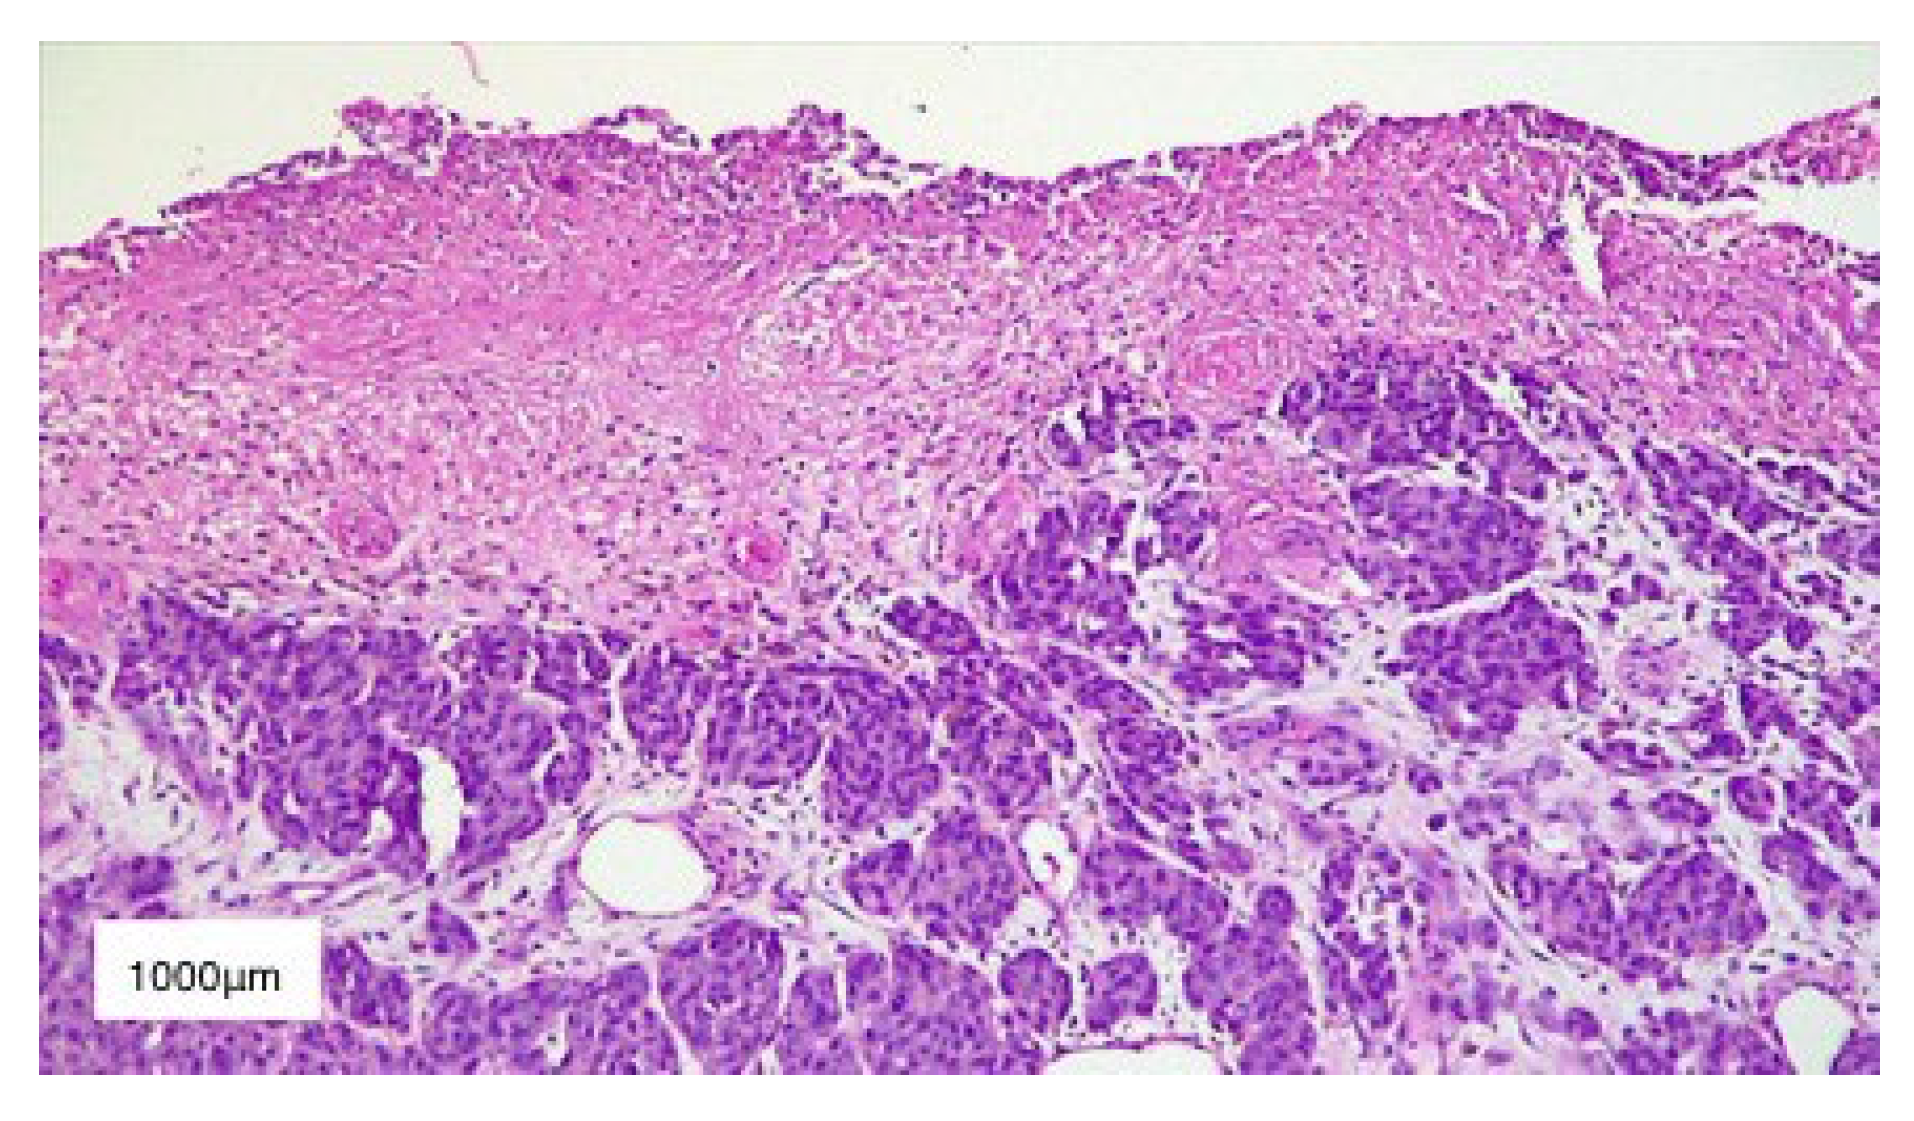

2. Case Presentation

3. Results